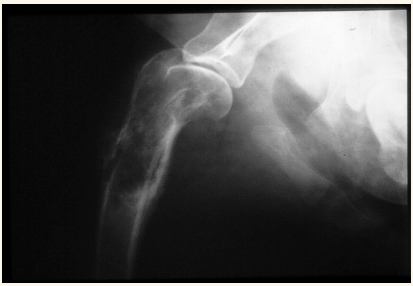

Humero:

Fracturas es lo mas comun, sobre todo en espiral. Pueden tener lesiones neuronales recuperables

Los sarcomas aparecen lejos del codo en extermidades anteriores y cerca de la rodilla en extermidades posteriores.

Las neoplasias sueln ser en la zona proximal del humero